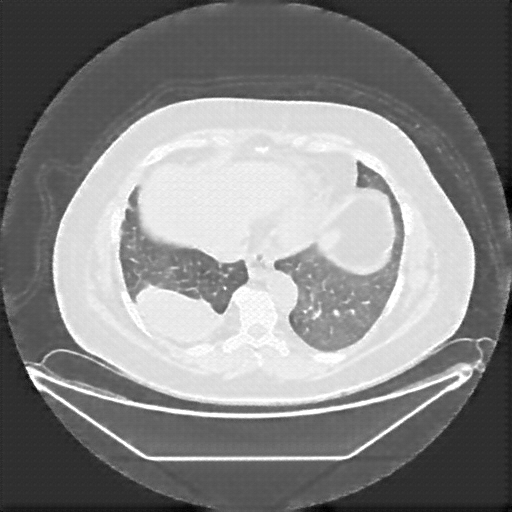

Image Grid

4Γ—3 grid: Rows show different image types (Original NATIVE, Reconstructed NATIVE, Original VENOUS, Generated VENOUS), Columns show windowing techniques (No Window, Lung Window, Mediastinum Window)

Original VENOUS CT scan

No window - Raw intensity values

Lung window (WL -600, WW 1500 β†’ Low βˆ’1350, High +150)

Mediastinum window (WL 40, WW 400 β†’ Low βˆ’160, High +240)

Generated VENOUS CT scan (A→B translation)